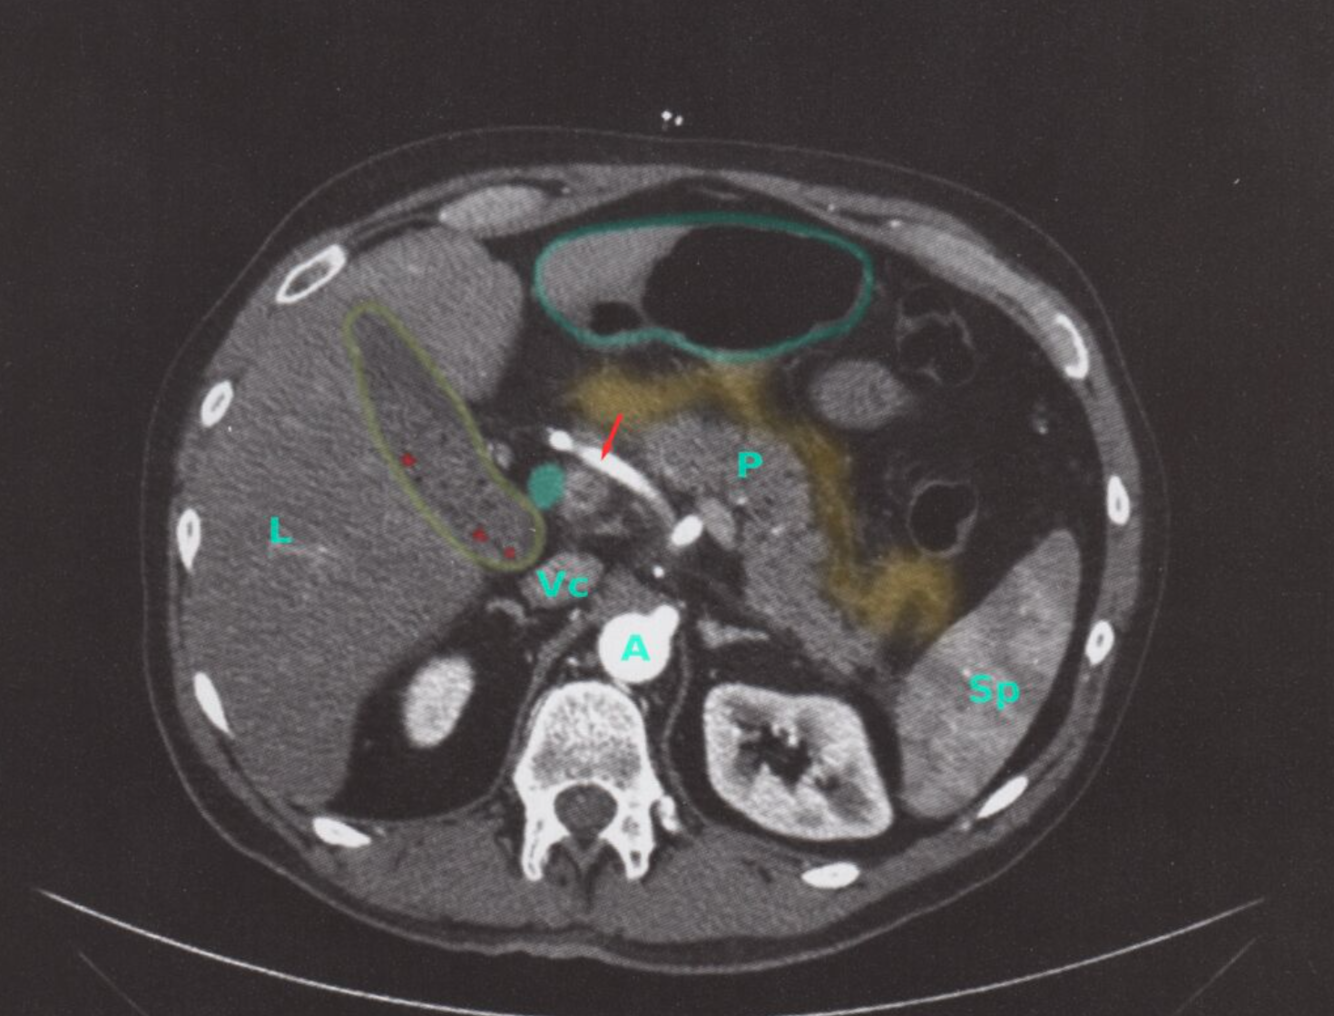

TDM de l’abdomen (avec contraste ; plan axial) d’un patient atteint de pancréatite biliaire aiguë

Un échouage graisseux et fascial (superposition jaune) antérieur au pancréas (P) indique une inflammation péripancréatique. La vésicule biliaire (contour jaune) contient des calculs (exemples indiqués par une superposition rouge) et des boues. De plus, le canal cholédoque (overlay vert) est légèrement dilaté.

Le passage d’un calcul de la vésicule biliaire à travers le canal cholédoque peut entraîner une pancréatite aiguë